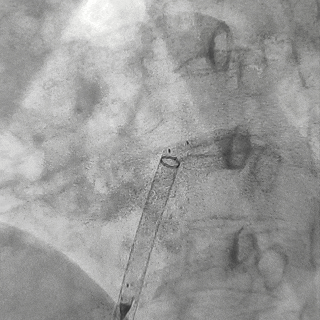

左盘展开

左盘展开后,牵拉成型线使其成型并将左盘后撤贴靠房间隔

DSA下可见左盘及腰部3个Mark点靠拢